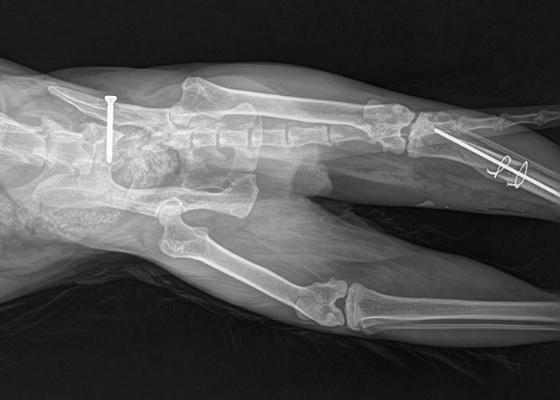

Balesetes cicánk, Tomi (Fülöpke) gyógyulgatása

TOMI cica gyógyulgatása

Nálunk járt H. Margó, aki ismeri a cicát az utcáról. Tőle tudjuk, hogy a balesetes Fülöpke eredeti neve TOMI. Szerencsére ivartalanított, akinek gazdája szociális otthonba költözött, és így ő évek óta az utcán élt. Többen etették, Margó is gyakran vitt neki finom falatokat. Mindig az utca ugyanazon az oldalán volt, mint aki soha nem járt volna át a tuloldalra.

De sajnos azon a végzetes szombat este mégis áthajtotta a kíváncsiság. Figyelmetlen volt, és megtörtént a baleset. Öt napja volt a műtéte. Az első két nap nagyon nehéz volt. Nem evett, nem ivott, fájdalmai voltak.        Ma már eszik, mosdik, rá tud feküdni a műtött oldalára is. Átbiceg az alomba. Törött lábán a véraláfutás sokat javult. Hangosan dorombol, ha leülünk mellé, vagy szólunk hozzá.

Balesetes cicánk, Fülöpke műtéte holnap lesz

A mai éjszakát az orvosi rendelőben tölti, infúzióval altatható állapotba hozzák, és holnap délelőtt műtik. A medencéje vagy 6 helyen eltört, letört a keresztcsontja, és a jobb hátsó lába is romokban van. Nagyon drukkolunk neki, hogy sikerüljön. Őt Noémi és párja találta Újszegeden, a Derkovits fasor 34-36. körül.

Tomi, akinek medencecsontja hat helyen, és jobb lába nagyon összetört egy balesetben 3 hete, a műtéte után szorgalmasan gyógyulgat, és már nagyon ügyesen tudja terhelni a lábát.